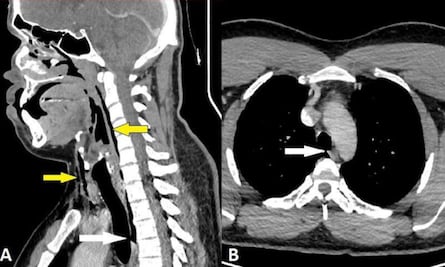

¿Contienes tus estornudos? Piénsalo dos veces: paciente sufre desgarramiento traqueal

Este tipo de daño es una 'afección rara y potencialmente mortal', aseguran médicos